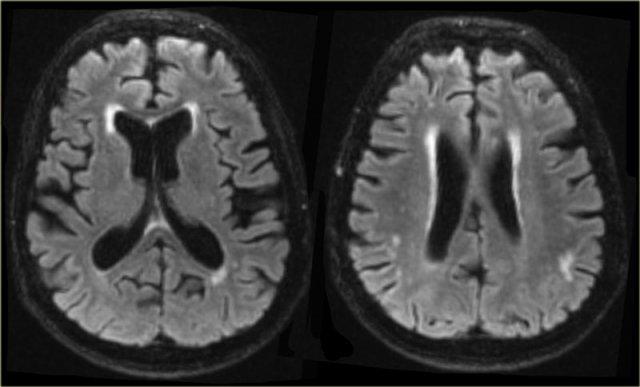

Ở hầu hết bệnh nhân VaD, có bệnh lý chất trắng lan tỏa với các tổn thương hợp lưu lớn (Fazekas 3).

Ở một số bệnh nhân này, não thất có thể giãn do teo não toàn thể và một số cũng có teo thùy thái dương trong.

Các hình ảnh là của một bệnh nhân mắc VaD, nhưng thùy thái dương trong bình thường.

Bên trái là hình ảnh của một bệnh nhân được chẩn đoán VaD.

Bệnh lý chất trắng được thấy dưới dạng tăng tín hiệu chất trắng nặng nề (giảm tín hiệu trên T1W) ở vùng quanh não thất.

Ngoài các thay đổi mạch máu này, còn có MTA.

Có thể bệnh nhân này mắc cả VaD và AD, một phát hiện thường gặp ở nhiều bệnh nhân cao tuổi.

Các dấu hiệu này cần được mô tả riêng biệt vì có thể có hệ quả điều trị.